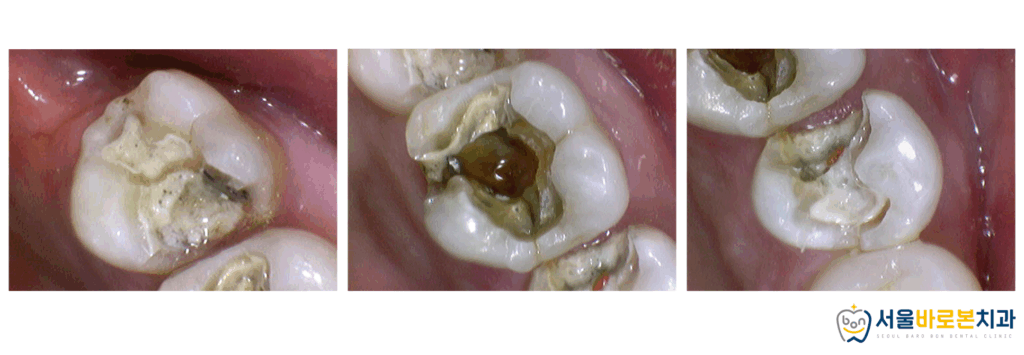

먼저 입안 상태를 볼까요?

치료를 아주 많이 받은 편은 아니셨지만

그래도 군데군데 금으로 제작한

인레이와 크라운이 눈에 띕니다.

오늘 소개해 드릴 치료 부위는

위 사진에 표시한 위쪽 어금니 부위인데요.

언뜻 보기에는 별문제가

없어 보일 수 있는 사진인데

대체 무엇이 문제일까요?

이번에는 옆면에서 더욱 자세하게

확인해 보도록 하겠습니다.

치아 사이 면이 무언가

까맣게 확인됩니다.

왼쪽 사진은 마치

치아에 멍이 든 것처럼 보이기도 하고,

오른쪽 사진은 갈색 반점이 눈에 띕니다.

2차 충치입니다.